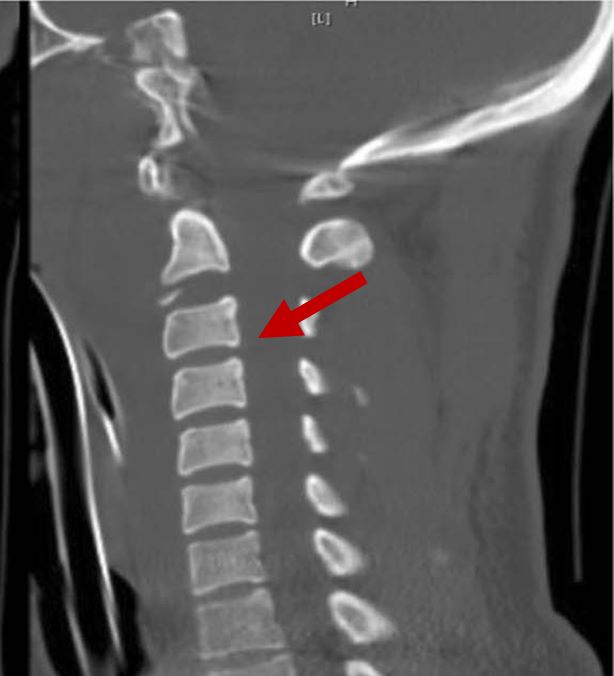

2D CT scan showing normal vertebrae

Radiographical features source 6